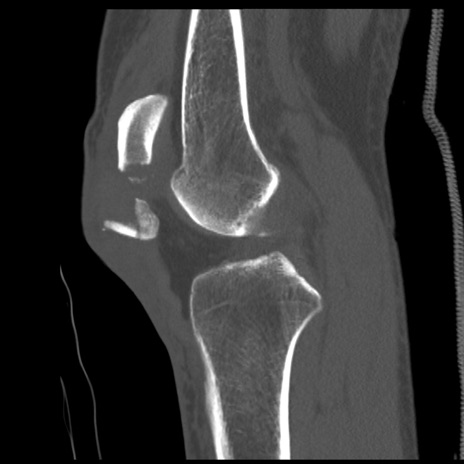

症例28 右膝関節CT(矢状断像)

異常所見と診断は?

右膝関節CT

冠状断像